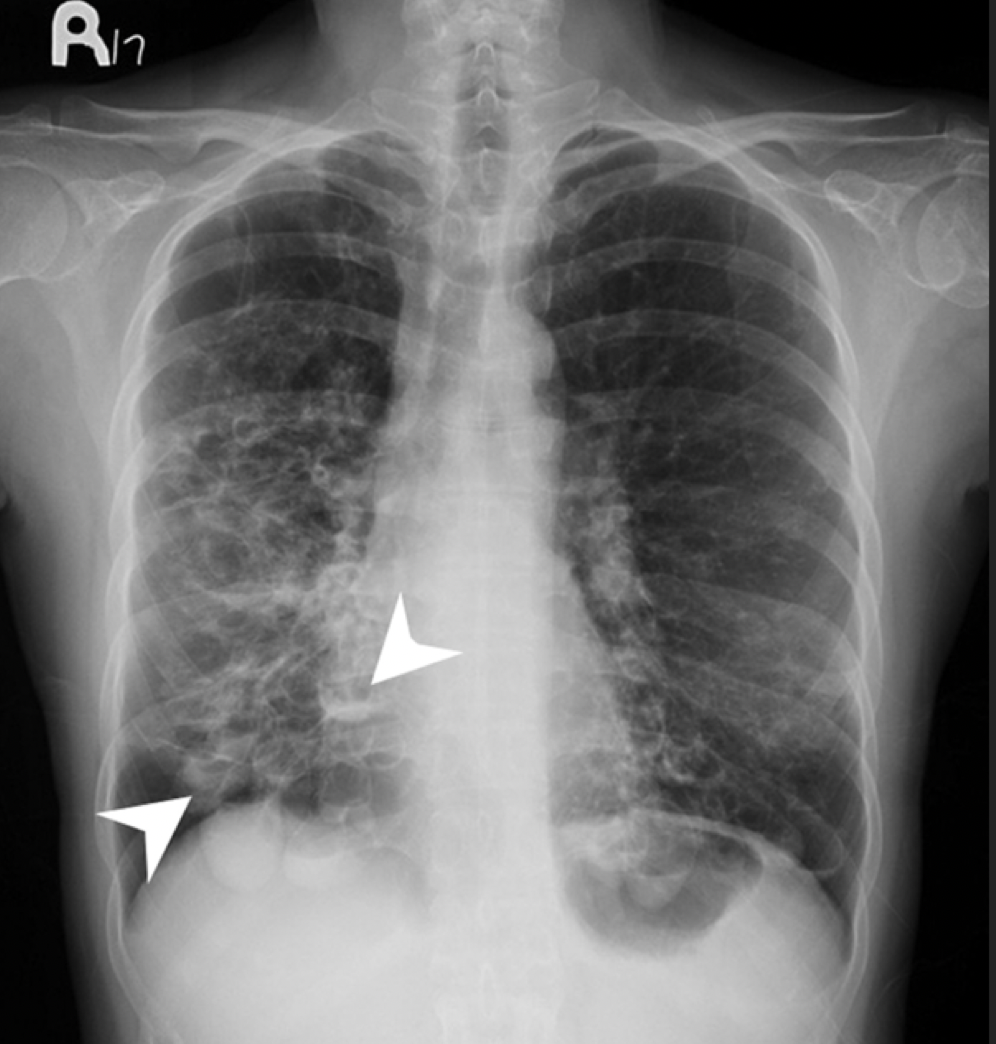

What are the XRay changes in a patient with Bronchiectasis?

A

• Exclude other causes

• Thickened bronchial walls

• Ring shadows (thickened airways seen end-on)

• Volume loss secondary to mucous plugging

• Air-fluid levels may be visible within dilated bronchi